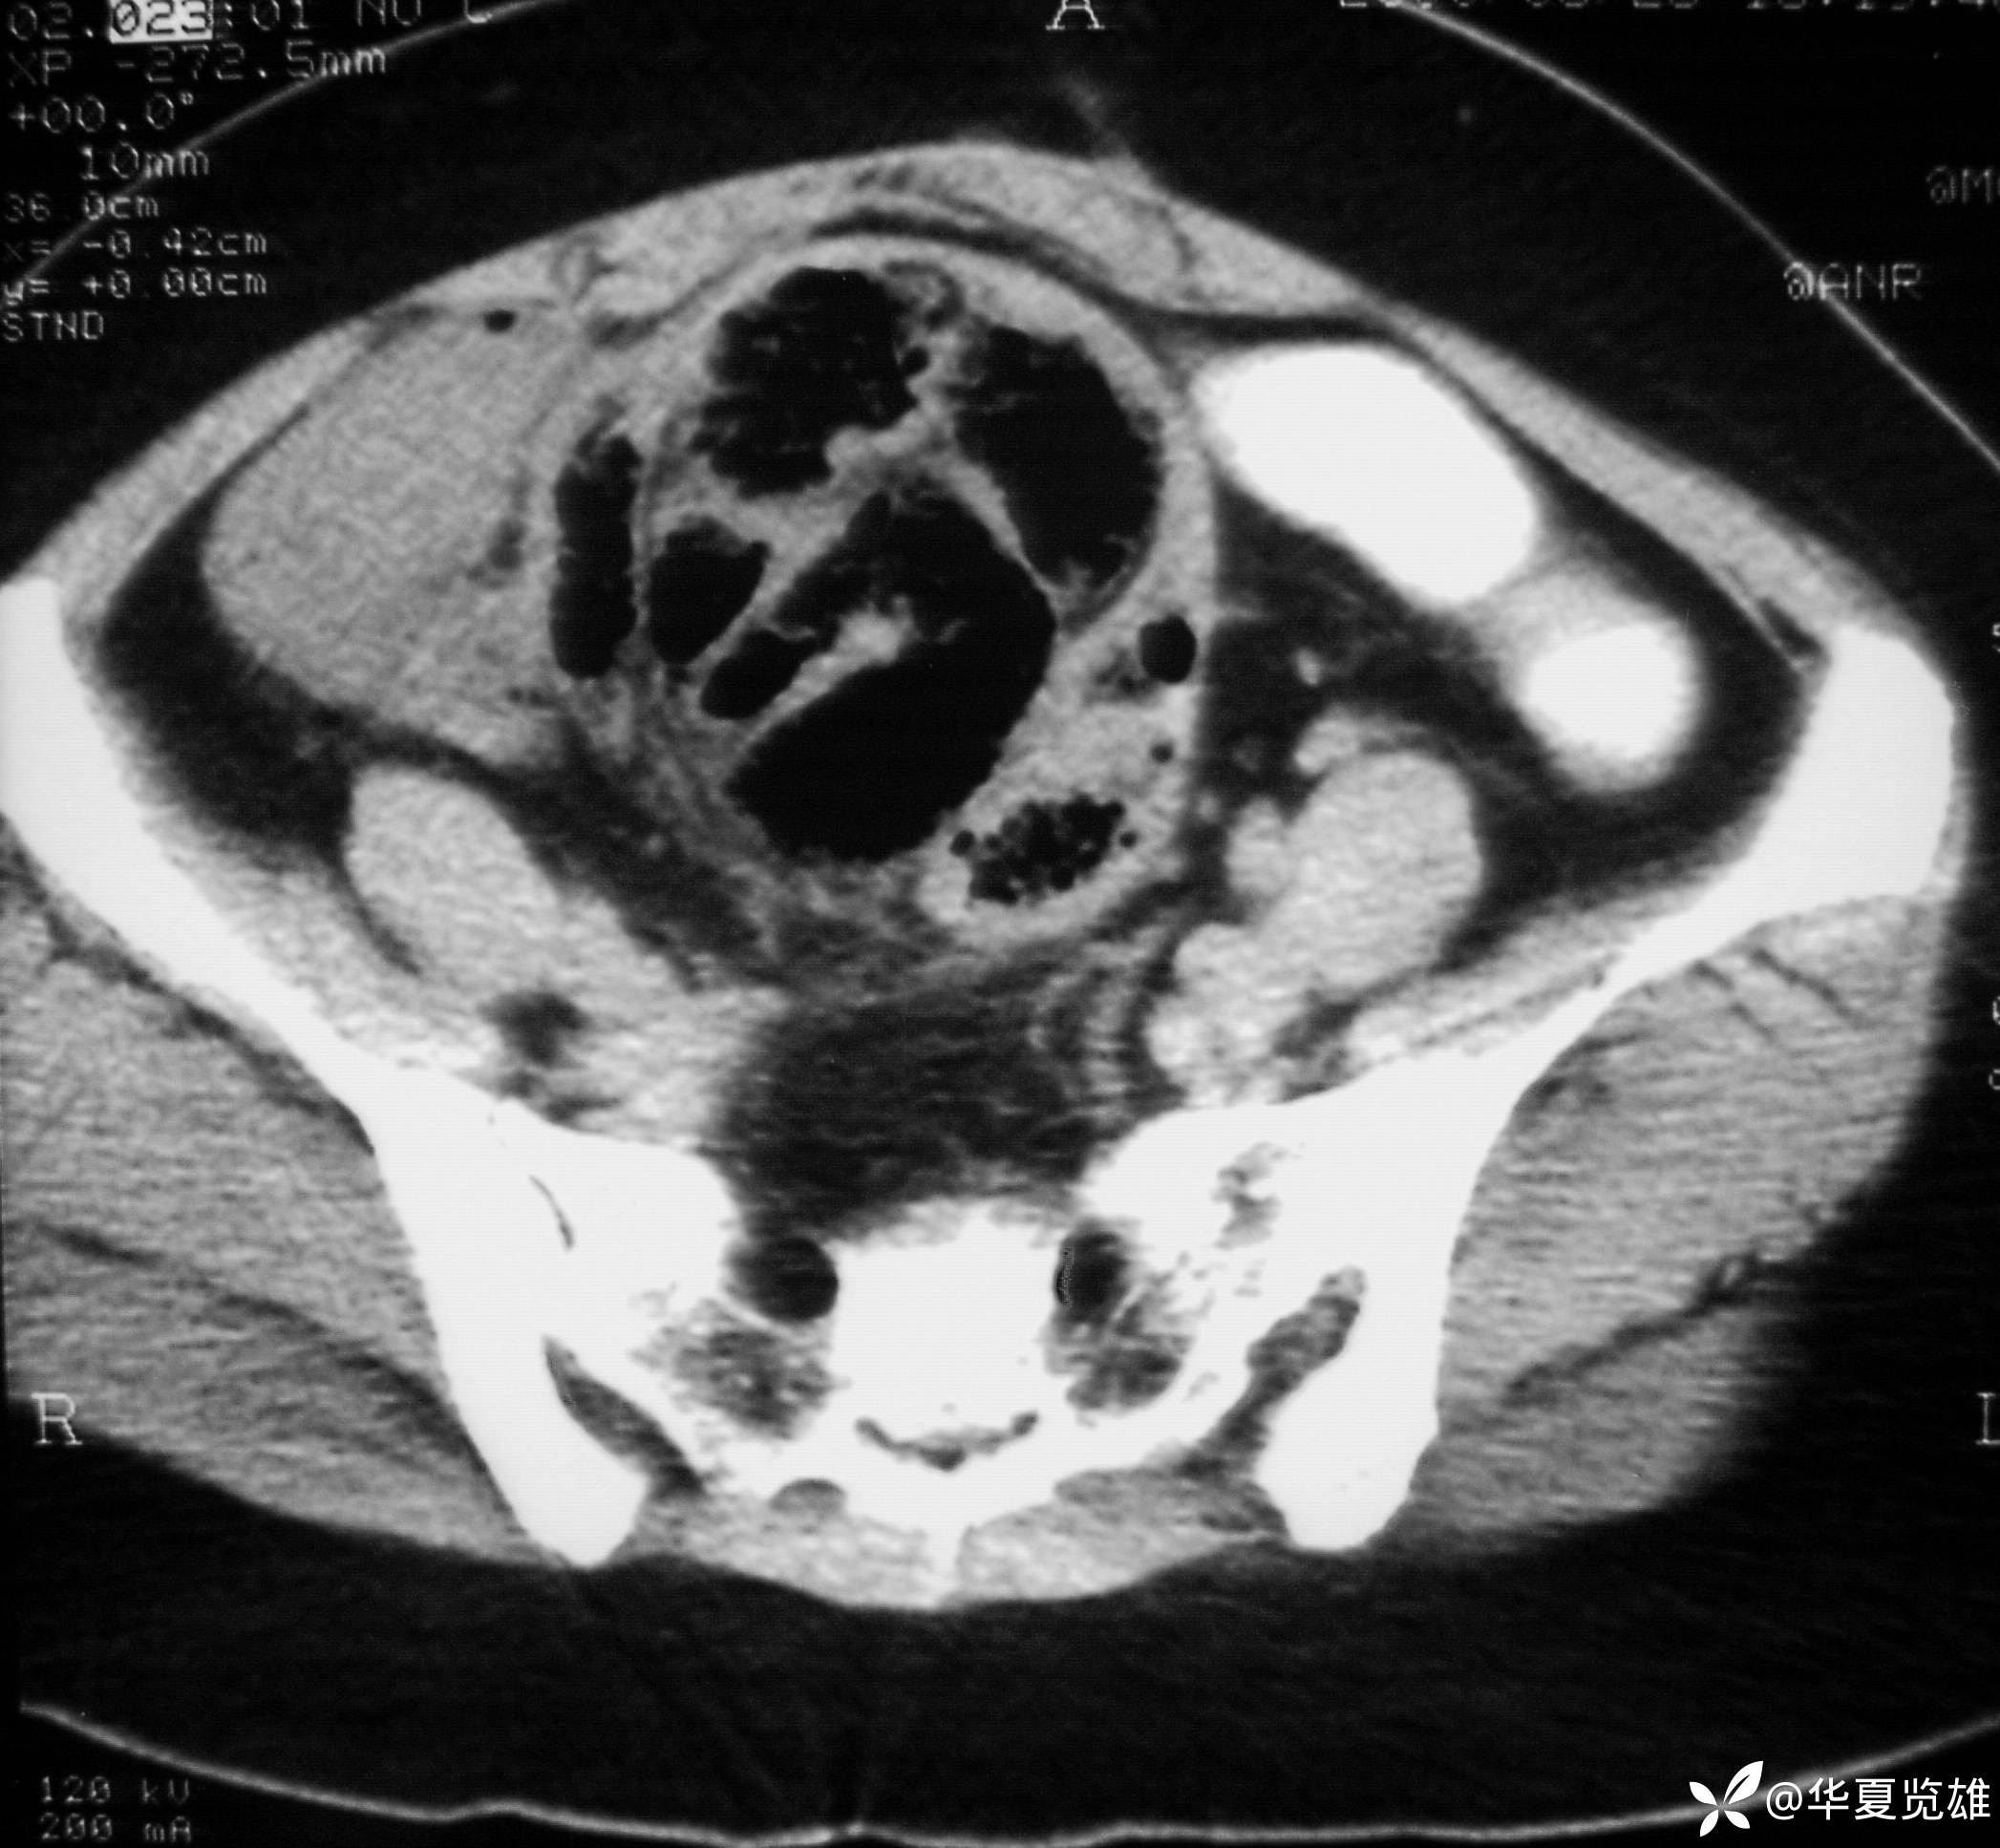

体格检查:下腹部有一纵形手术瘢痕。腹部压痛,无反跳痛。中下腹部扪及一12 cm× 18 cm包块,质韧,压痛。肠鸣音亢进,未闻及气过水音。

红箭-入口;绿箭-出口